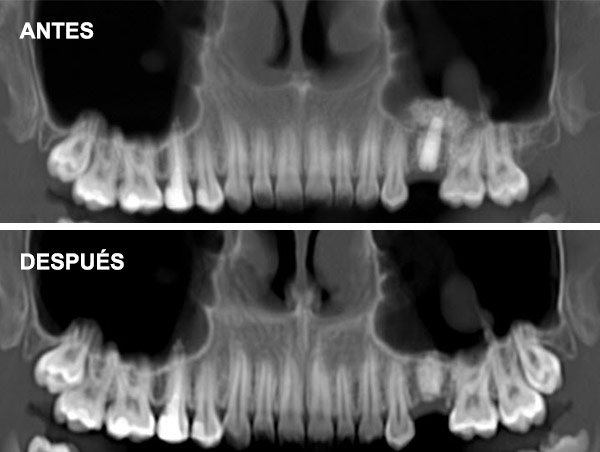

Esta técnica consiste en aumentar la altura y anchura del hueso en los maxilares introduciéndonos en el seno para conseguir una base ósea que permita la colocación de implantes.

Es un procedimiento sencillo que se realiza con anestesia local. Se practica una pequeña incisión a la altura de las raíces de los molares y premolares del maxilar superior, se crea una ventana en el hueso para acceder a la cavidad sinusal y se eleva la membrana para colocar un injerto de hueso en el suelo del seno maxilar.

Cuando no hay hueso ni distancia suficiente entre el maxilar superior y el seno (altura menor a 5 mm) que imposibilita la colocación de implantes.